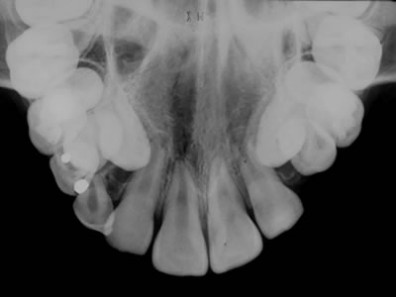

Radiografia Oclusal

Técnica radiográfica onde se utiliza um sensor radiográfico de maiores dimensões, abrangendo na imagem grande parte da maxila ou mandíbula, dependendo da área que se pretende analisar (Oclusal súpero-anterior, transversal da maxila, superior lateral, ínfero-anterior, transversal da mandíbula ou oclusal inferior lateral).